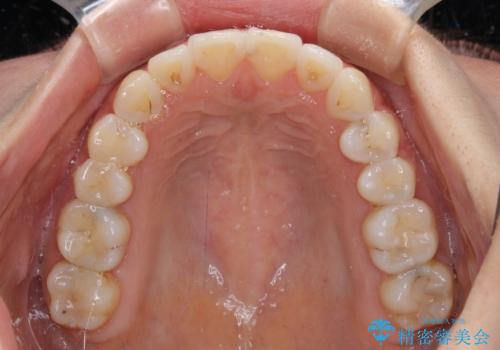

- 上下前歯のデコボコを気にして来院された患者様です。

インビザラインによる上下歯列の拡大と、IPR(歯と歯の間を削る)にるスペースの獲得により、前歯のデコボコを改善することとしました。

しっかりと装着時間を遵守してくださったので、思い通りの歯列に整えることができました。

結婚式前に終了させることができ、患者様には大変満足していただきました。